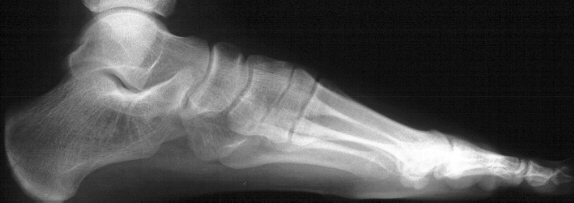

This

condition is usually thought to be autosomal dominant inheritance

with variable penetrance.

The

etiology of the above problem appears to be a defect in segmentation

and differentiation of the primitive mesenchyme

A

conservative treatment of casting and orthotic use has no scientific

basis of support for this condition.

etiology of the spastic flat foot is a neurologic response to

inflammation in the subtalar joint causing spasticity of the peroneal

muscles.

Because

additional coalitions occur in 15 percent of the feet with a talonavicular

coalition, a CT scan of the talocalcaneal joint is required prior

to excision of the talonavicular bar.